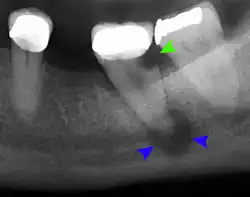

Decay (green) with apical abscess (blue) -

Gutta-percha point indicating abscess origin